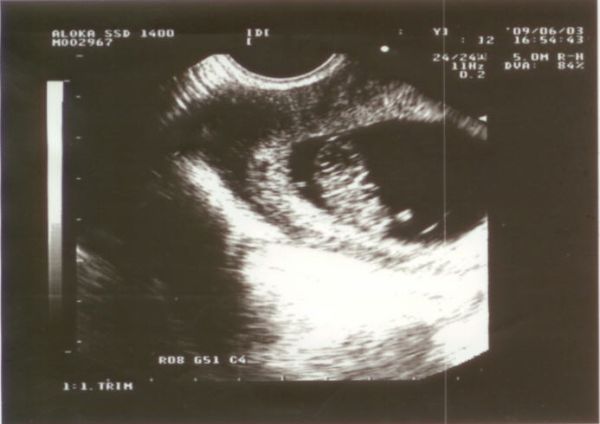

Kép 6 hetesen az első ultrahangon

Sziasztok. először is feltenném az első ultrahangos képet amikor 6 hetesen voltunk a dokinál és már hallottuk a szívdobogását.